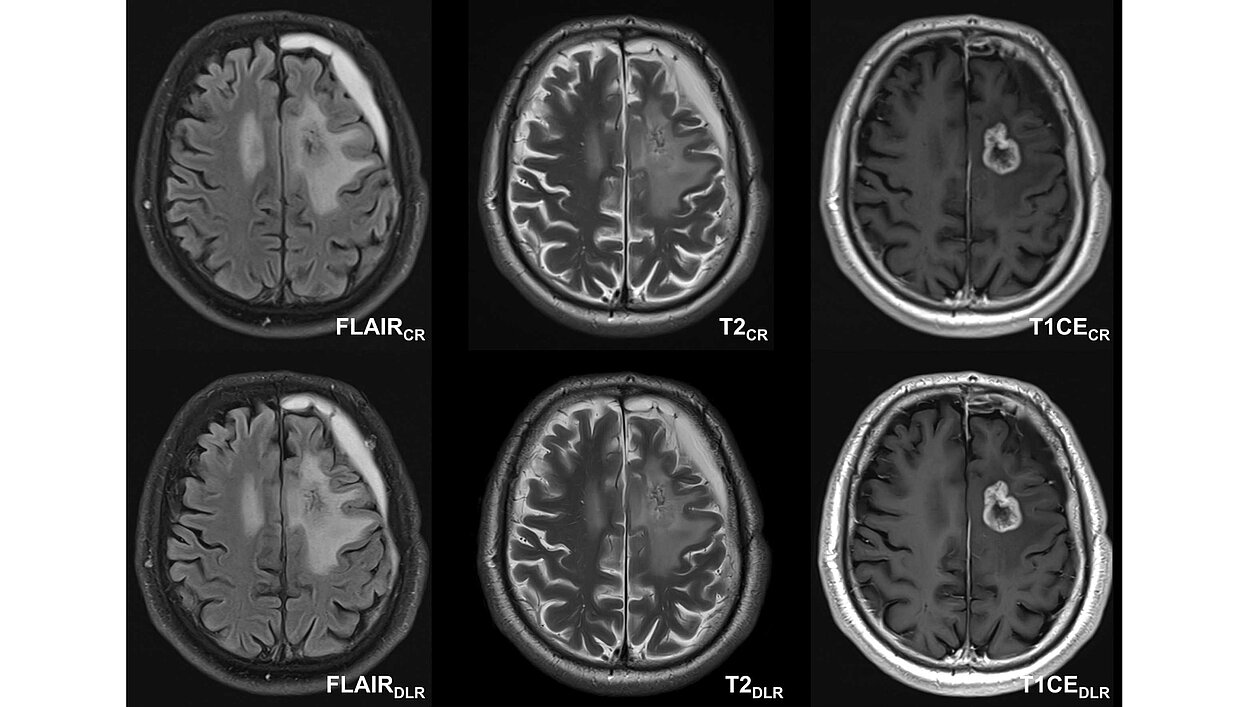

Eine aktuelle Studie des Universitätsklinikums Tübingen untersuchte das Potenzial von mittels Deep Learning rekonstruierten (DLR) Bildern in der Magnetresonanztomographie (MRT) bei IDH-mutierten Gliomen im Vergleich zur traditionellen Bildgebung (CR). Durchgeführt wurde die Studie von einem interdisziplinären Team aus der Neuroradiologie, der Neurochirurgie, Neuroonkologie und Strahlentherapie. Ziel war es, die Messzeitverkürzung, Bildqualität und diagnostische Sicherheit von DLR-Bildern in einem umfassenden diagnostischen MRT-Protokoll zu bewerten, das kontrastmittelverstärkte T1-gewichtete, T2-gewichtete Turbo-Spin-Echo- (TSE) und FLAIR-Sequenzen umfasst.

Bildqualität: DLR erhielt durchgehend höhere Bewertungen der qualitativen Bildqualität von allen Gutachtenden und über alle Sequenzen hinweg. Die Tumorsichtbarkeit bei DLR war im Vergleich zu CR-Bildern nicht schlechter.

Verbesserte Kennzahlen: Die quantitative Analyse zeigte signifikante Verbesserungen im Signal-Rausch-Verhältnis (SNR) und Kontrast-Rausch-Verhältnis (CNR) bei DLR im Vergleich zu CR. Größenmessungen von Läsionen ergaben keine signifikanten Unterschiede zwischen CR- und DLR-Sequenzen gemäß den Kriterien zur Tumorbewertung und dem Therapieansprechen (RANO-2.0-Kriterien).

Die Studie kam zu dem Schluss, dass DLR für die MRT-Bildgebung von IDH-mutierten Gliomen klinisch praktikabel ist. DLR bietet signifikante Zeitersparnisse (durchschnittliche Reduktion der Akquisitionszeit um 29,6%), ohne die Bildqualität oder diagnostische Genauigkeit zu beeinträchtigen. Die starke Präferenz für DLR im interdisziplinären Team unterstreicht das Potenzial, neuroonkologische Arbeitsabläufe zu optimieren und die Entscheidungsfindung zu verbessern.